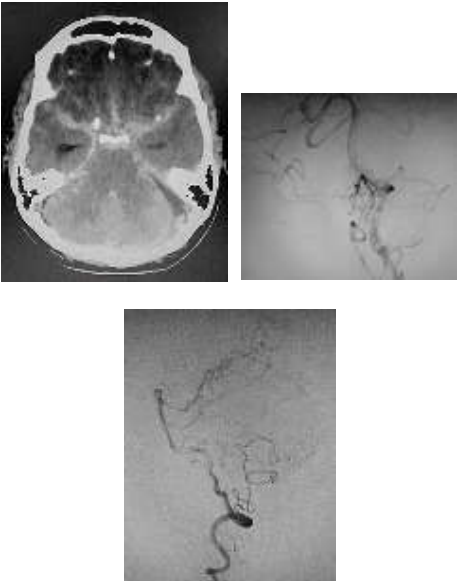

Homem de 53 anos apresentou cefaleia súbita, vômitos e alteração do nível de consciência. Após intubação orotraqueal e suporte clínico, foi realizada tomografia de crânio seguida de angiografia digital cerebral (imagens abaixo).

Assinale a alternativa que apresenta o melhor tratamento para esse caso.